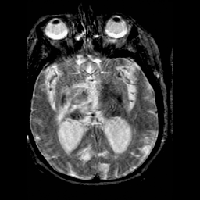

To further define the lesion, a cranial MRI with intravenous gadolinium is obtained. The MRI also demonstrates bilateral thalamic mass lesions with significant enhancement following IV administration of gadolinium. Again, hydrocephalus and mass effect are demonstrated. The dense signal characteristics are suggestive of a highly cellular tumor such as a primitive neuro-ectodermal tumor (PNET) or lymphoma.

Cranial MRI Images |